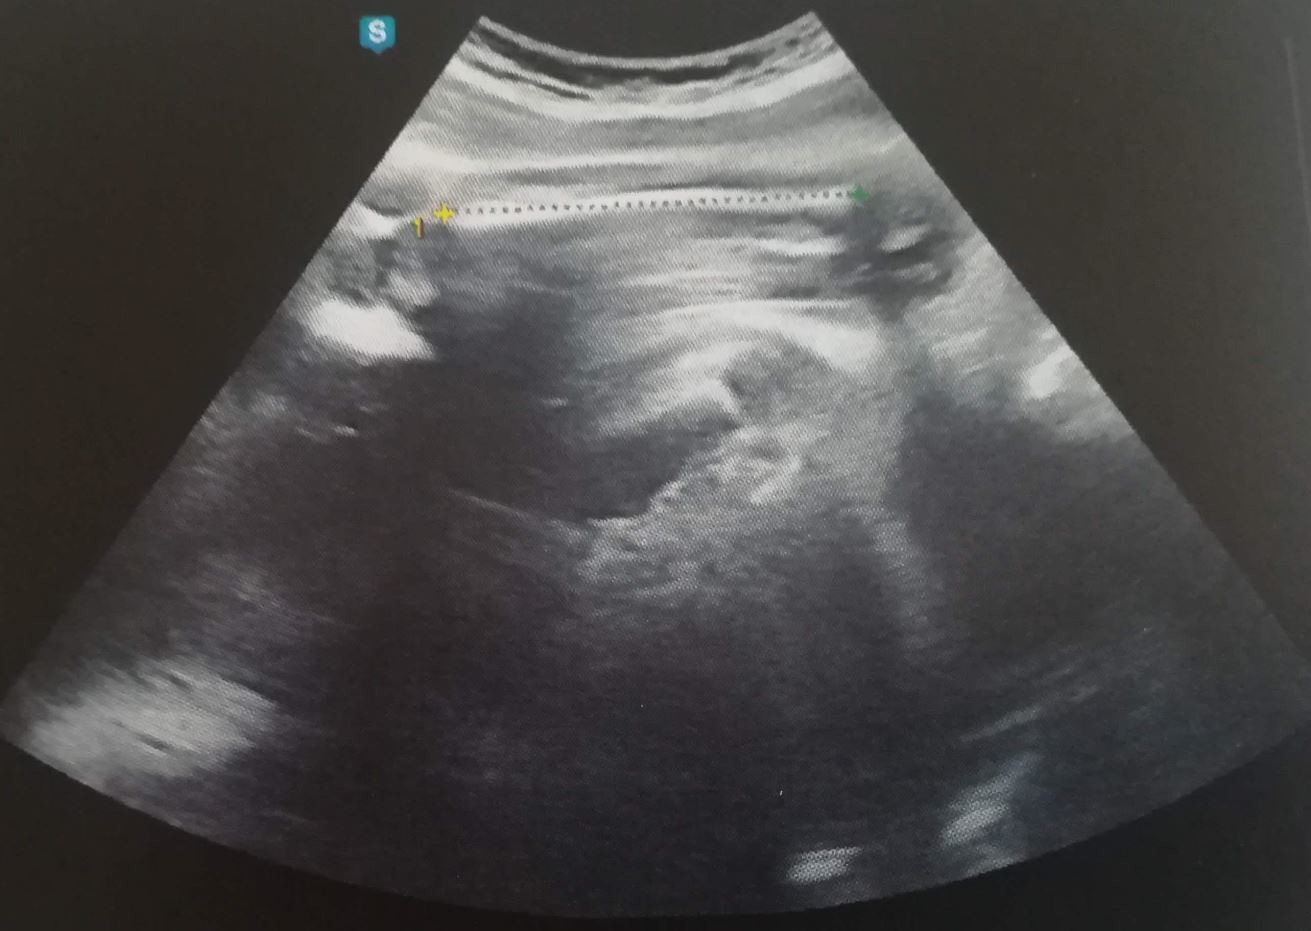

L'échographie du 2ème trimestre entre 21 et 23 SA Elle permet l'analyse morphologique détaillée du fœtus, organe par organe, afin de dépister d'éventuelles malformations L'échographie du 3ème trimestre vers 32 SA Elle permet de vérifier la bonne croissance fœtale, la 3e écho, les détails Appelée échographie « biométrique et morphologique », elle est réalisée entre la 32e et la 34e semaine d'aménorrhée (décompte à partir du 1er jour des dernières règles), soit la 30e et la 32e semaine de votre grossesse;On declancher a 8 mois et 15jrs car il pensait k il pesait ke 2kg100 et au final il pesait 2kg650 faut pas se fier au echographie ce n est pas au juste 14 Merci Merci Réponse 4 / 7 titema sept 10 à 1726

Pour les futurs parents, l'estimation du poids fœtal à l'échographie permet de s'imaginer un peu mieux ce bébé tant attendu Pour l'équipe médicale, cette donnée est essentielle Elle doit s'effectuer aux alentours de 32 SA (fin du septième, début du huitième mois) Le docteur Gilles Grangé explique « C'est une confirmation notamment de la croissance du bébé On va regarder la position du placenta, s'il n'est pas sur le col de l'utérus, la quantité de liquide et aussi les malformations possiblesRetrouvez toutes les anecdotes de ce 7ème mois de grossesse sur mon blog http//wwwbloghappychantillycom/magrossessede6a7mois

Le bébé à la SA 30 À la semaine 30 d'aménorrhée, le bébé mesure environ 40 centimètres des pieds à la tête et pèse environ 1400 grammes Ses organes internes sont pratiquement développés et fonctionnent de façon indépendante La maturation des poumons et le tube digestif sont presque terminés à 100% 32 SA 30 semaines de grossesse C'est probablement au cours de cette semaine que vous allez faire votre dernière échographie L'occasion de voir votre bébé encore une fois avant votre grande rencontre !A ce stade de grossesse, votre futur bébé est déjà trop gros pour que l'échographiste puisse le voir dans son intégralité

Pendant le suivi de la grossesse, on va vous proposer 3 échographies, qui sont celles habituellement recommandées Aucune des trois n'est obligatoire, mais elles sont fortement recommandées, pour vérifier le bon déroulement de la grossesse, et le bienêtre de votre bébé A 12, 22 et 32 semaines d'aménorrhéeEchographie de Raphaël à 32 SAEntre 32 et 33 semaines de grossesse, la taille du bébé est généralement de 435 à 440 mm Le poids moyen d'un enfant à ce moment est de grammes Dans les grossesses multiples, ces chiffres peuvent être différents Cela dépend en grande partie du nombre de bébés qu'une femme porte en même temps